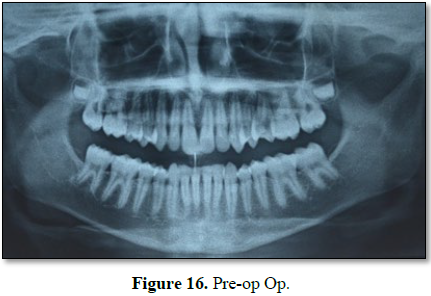

CASE REPORT III

Another case with exactly similar clinical presentation, radiographic

finding, histopathological reporting and immediate recovery after similar

intervention procedure irt to 24,25, but this time the lesion was unilateral

and in maxilla (Figures 15-19).